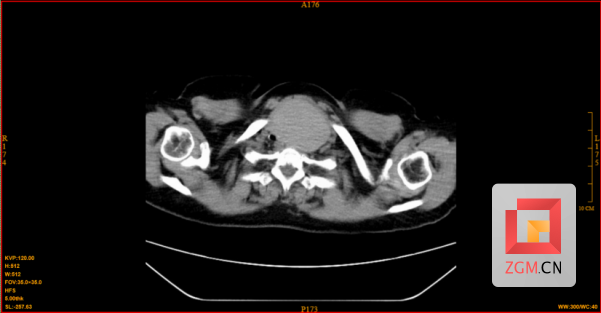

今年66岁的何阿姨,因“喘息、呼吸困难”就诊于呼吸与危重症医学科。经影像学检查发现,其甲状腺左叶存在一个约6.8cm的囊实性肿物,气管明显受压右移,最窄处仅约3.86mm,狭窄程度超过70%,同样面临极高的窒息风险。